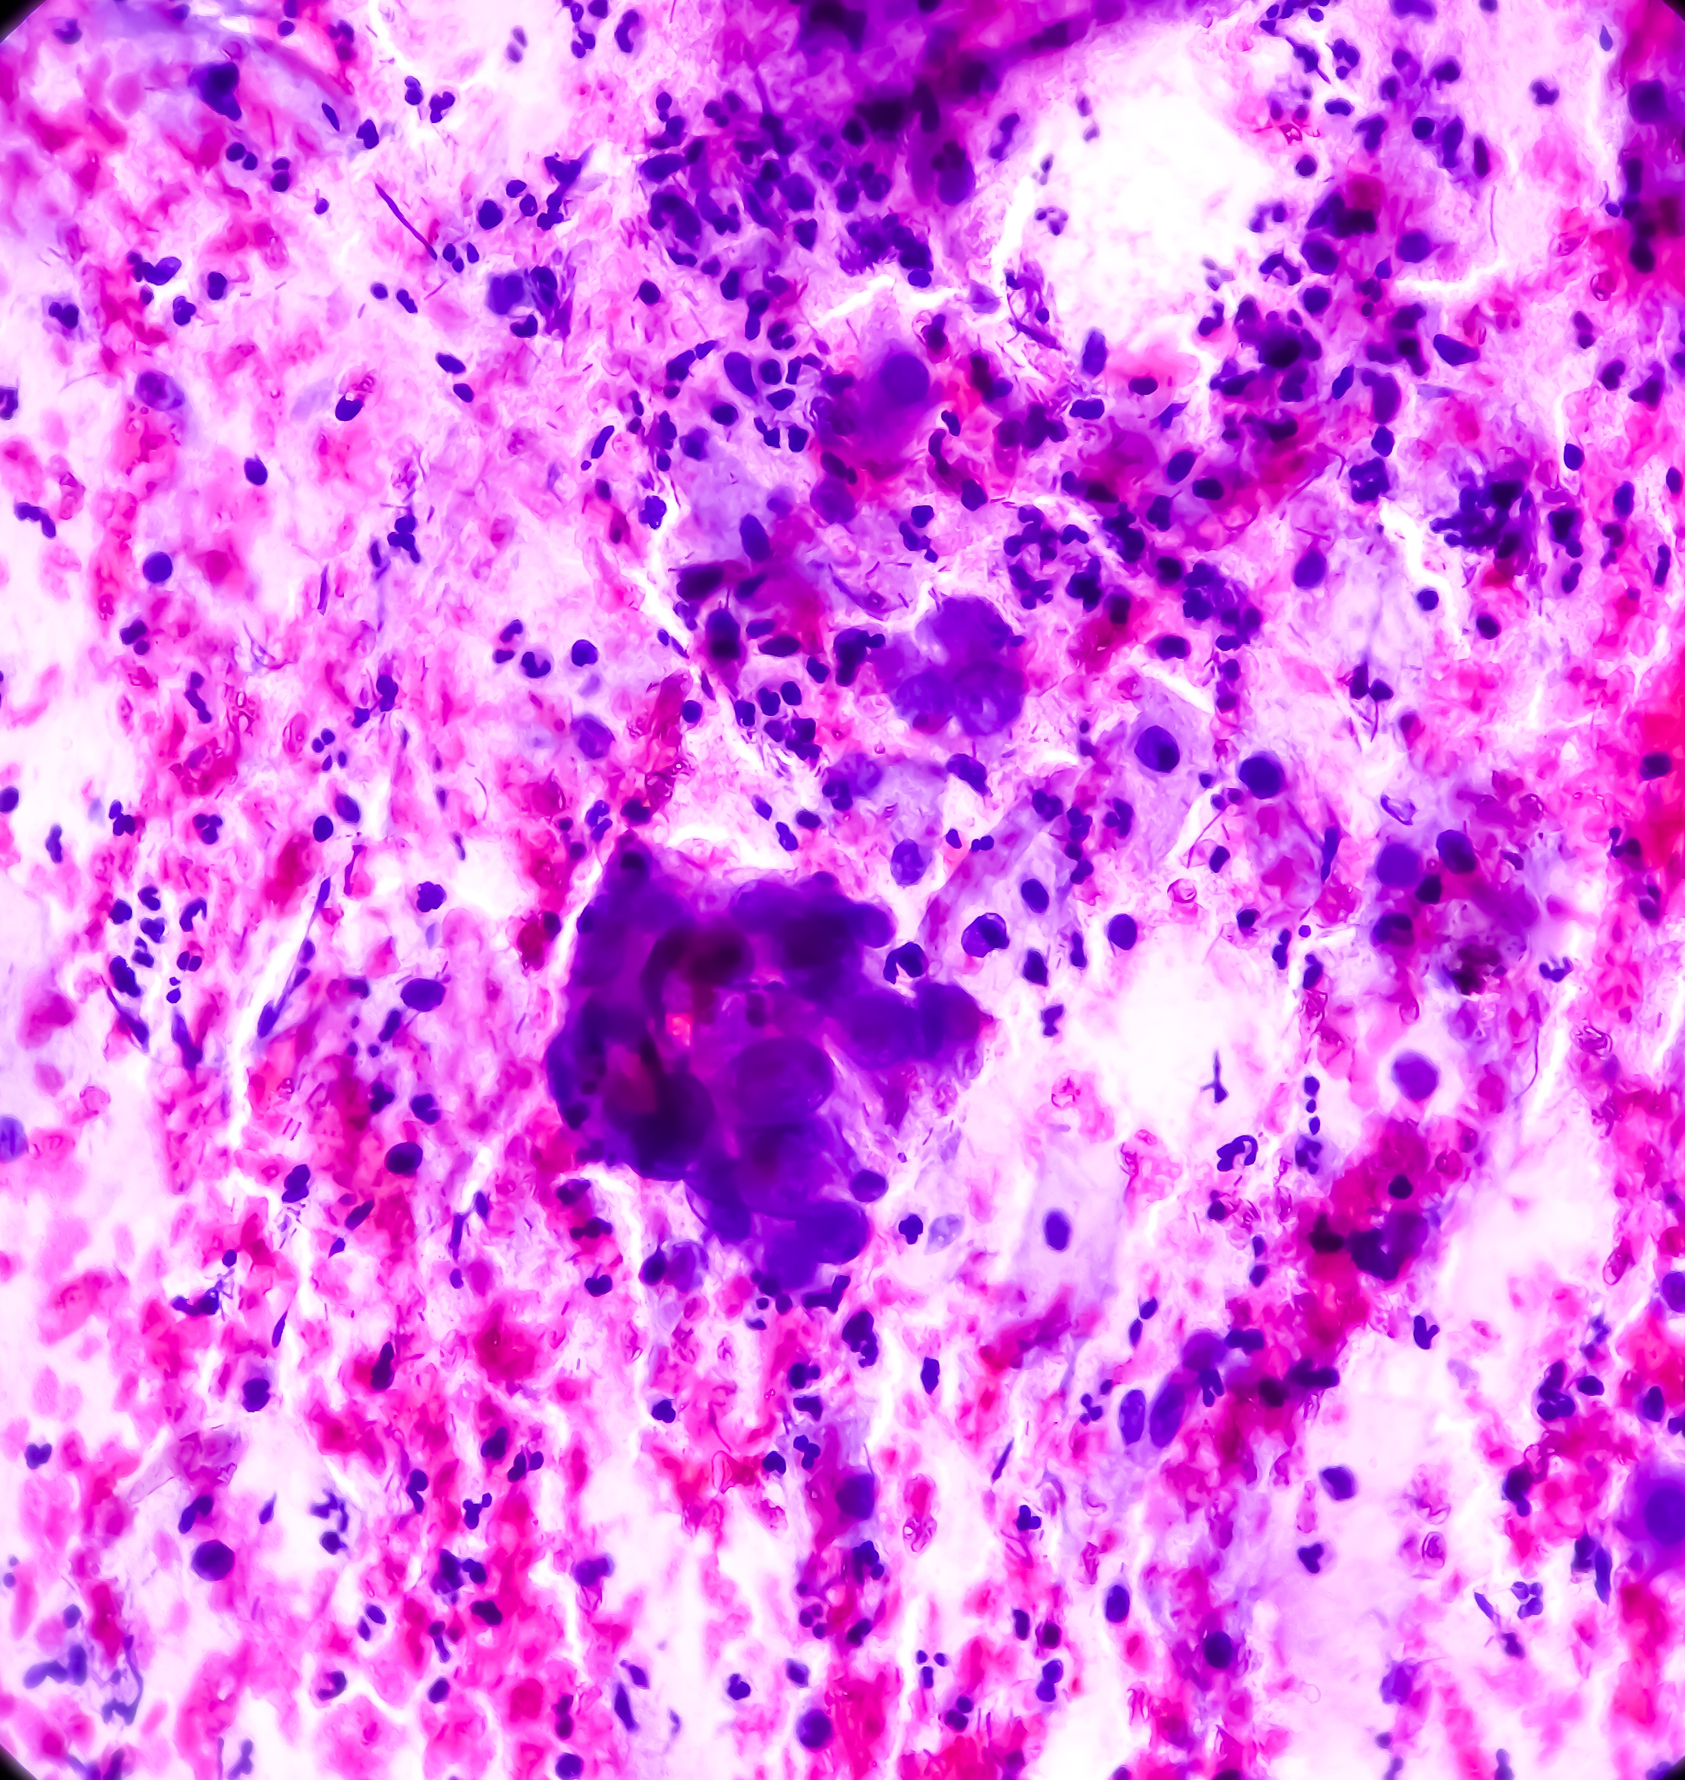

Types of vulval cancer include: